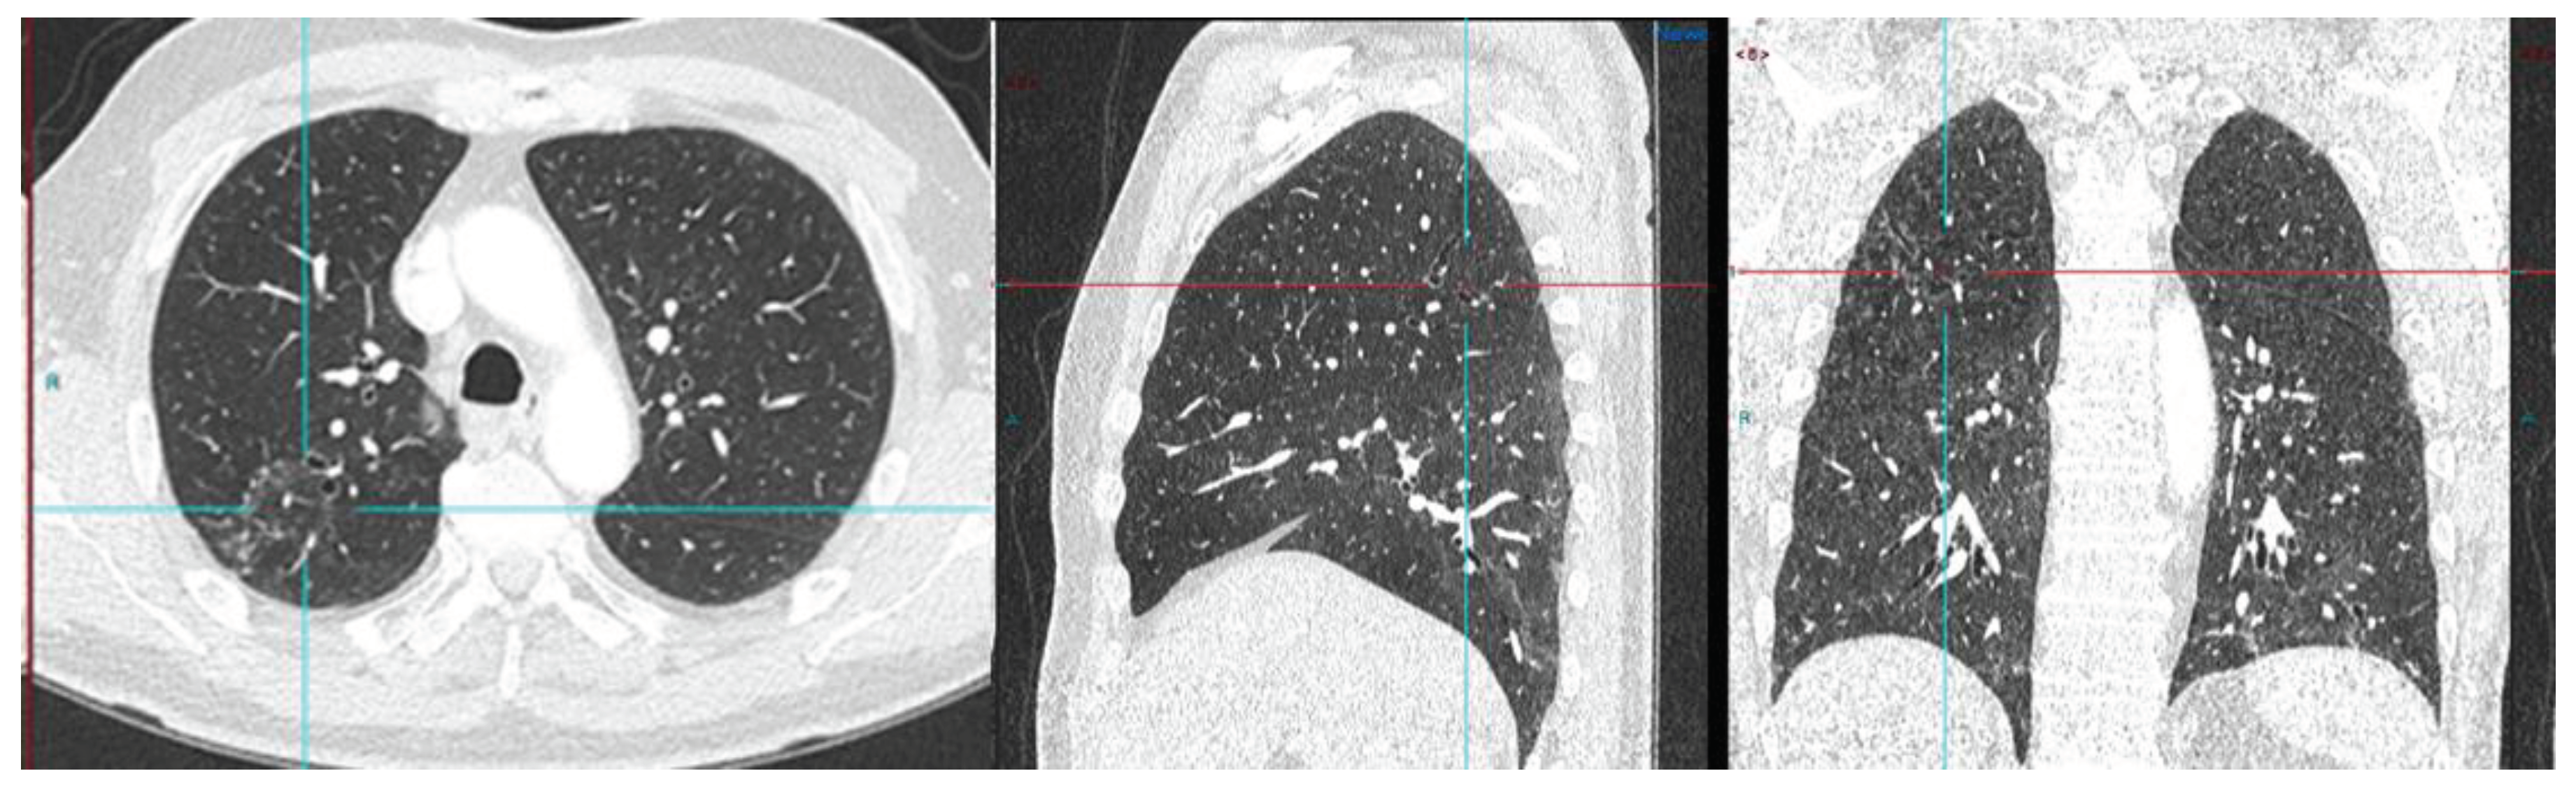

Image 3. PSA 0.9 ng/ml. Positive lymph node metastasis and suspicious uptake in prostate.